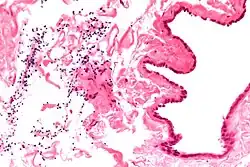

| Ultrasound of a testicle (grey) and a spermatocele (black). | |

Spermatocele is a fluid-filled cyst that develops in the epididymis.[3] The fluid is usually a clear or milky white color and may contain sperm.[4] Spermatoceles are typically filled with spermatozoa[5] and they can vary in size from several millimeters to many centimeters. Small spermatoceles are relatively common, occurring in an estimated 30 percent of males.[6] They are generally not painful. However, some people may experience discomfort such as a dull pain in the scrotum from larger spermatoceles.[7] They are not cancerous, nor do they cause an increased risk of testicular cancer. Additionally, unlike varicoceles, they do not reduce fertility.[7]

The primary care physician may diagnose and manage benign causes of scrotal masses such as hydrocele, varicocele and spermatocele. However, if a "must not miss" diagnosis related to testicular masses such as testicular torsion, epididymitis, acute orchitis, strangulated hernia and testicular cancer is suspected, the family physician must refer to a urologist.[19] Finding a painless, cystic mass at the head of the epididymis that is clearly separate from the testicle can indicate a spermatocele. Shining a light through the mass, a process known as transillumination, can also help differentiate between a fluid-filled cyst and a tumor, which would not allow as much light to pass.[20] If uncertainty exists, ultrasonography of the scrotum can confirm the presence of a spermatocele.[7] The location and history of any scrotal masses are crucial in determining whether or not the mass is benign or malignant.[21] Lab tests such as a complete blood count (CBC test) or urine test can also be conducted to check for any possible infection or signs of inflammation.[22]

Spermatoceles come in varying sizes and shapes. Some spermatoceles are very small and can only be detected through an ultrasound. More commonly seen are spermatoceles that are a pea-sized lump. They tend to form above or behind a testicle and have a shape and size that looks like a pea. Larger growths have been reported to look similar to a third testicle and can be very discomforting.[22] For those who are affected with large spermatoceles, some have reported feeling pain, heaviness, and fullness in the affected testicle.[20]